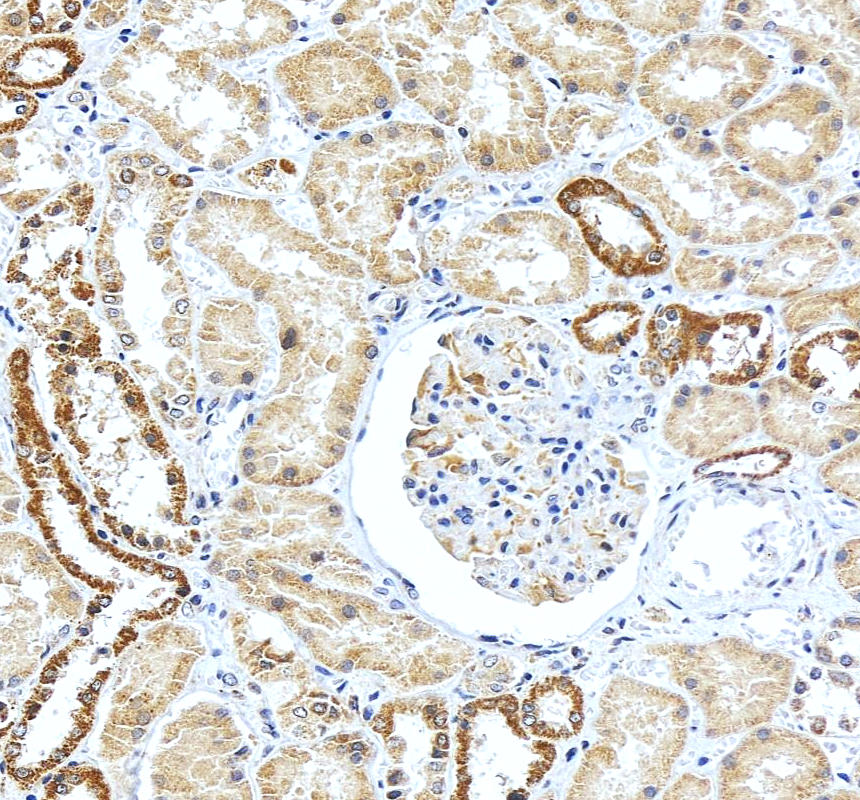

IHC analysis of LEPR using anti-LEPR antibody (BA1234).

LEPR was detected in a paraffin-embedded section of human kidney tissue. The tissue section was incubated with rabbit anti-LEPR Antibody (BA1234) at a dilution of 1:200 and developed using HRP Conjugated Rabbit IgG Super Vision Assay Kit (Catalog # SV0002) with DAB (Catalog # AR1027) as the chromogen.